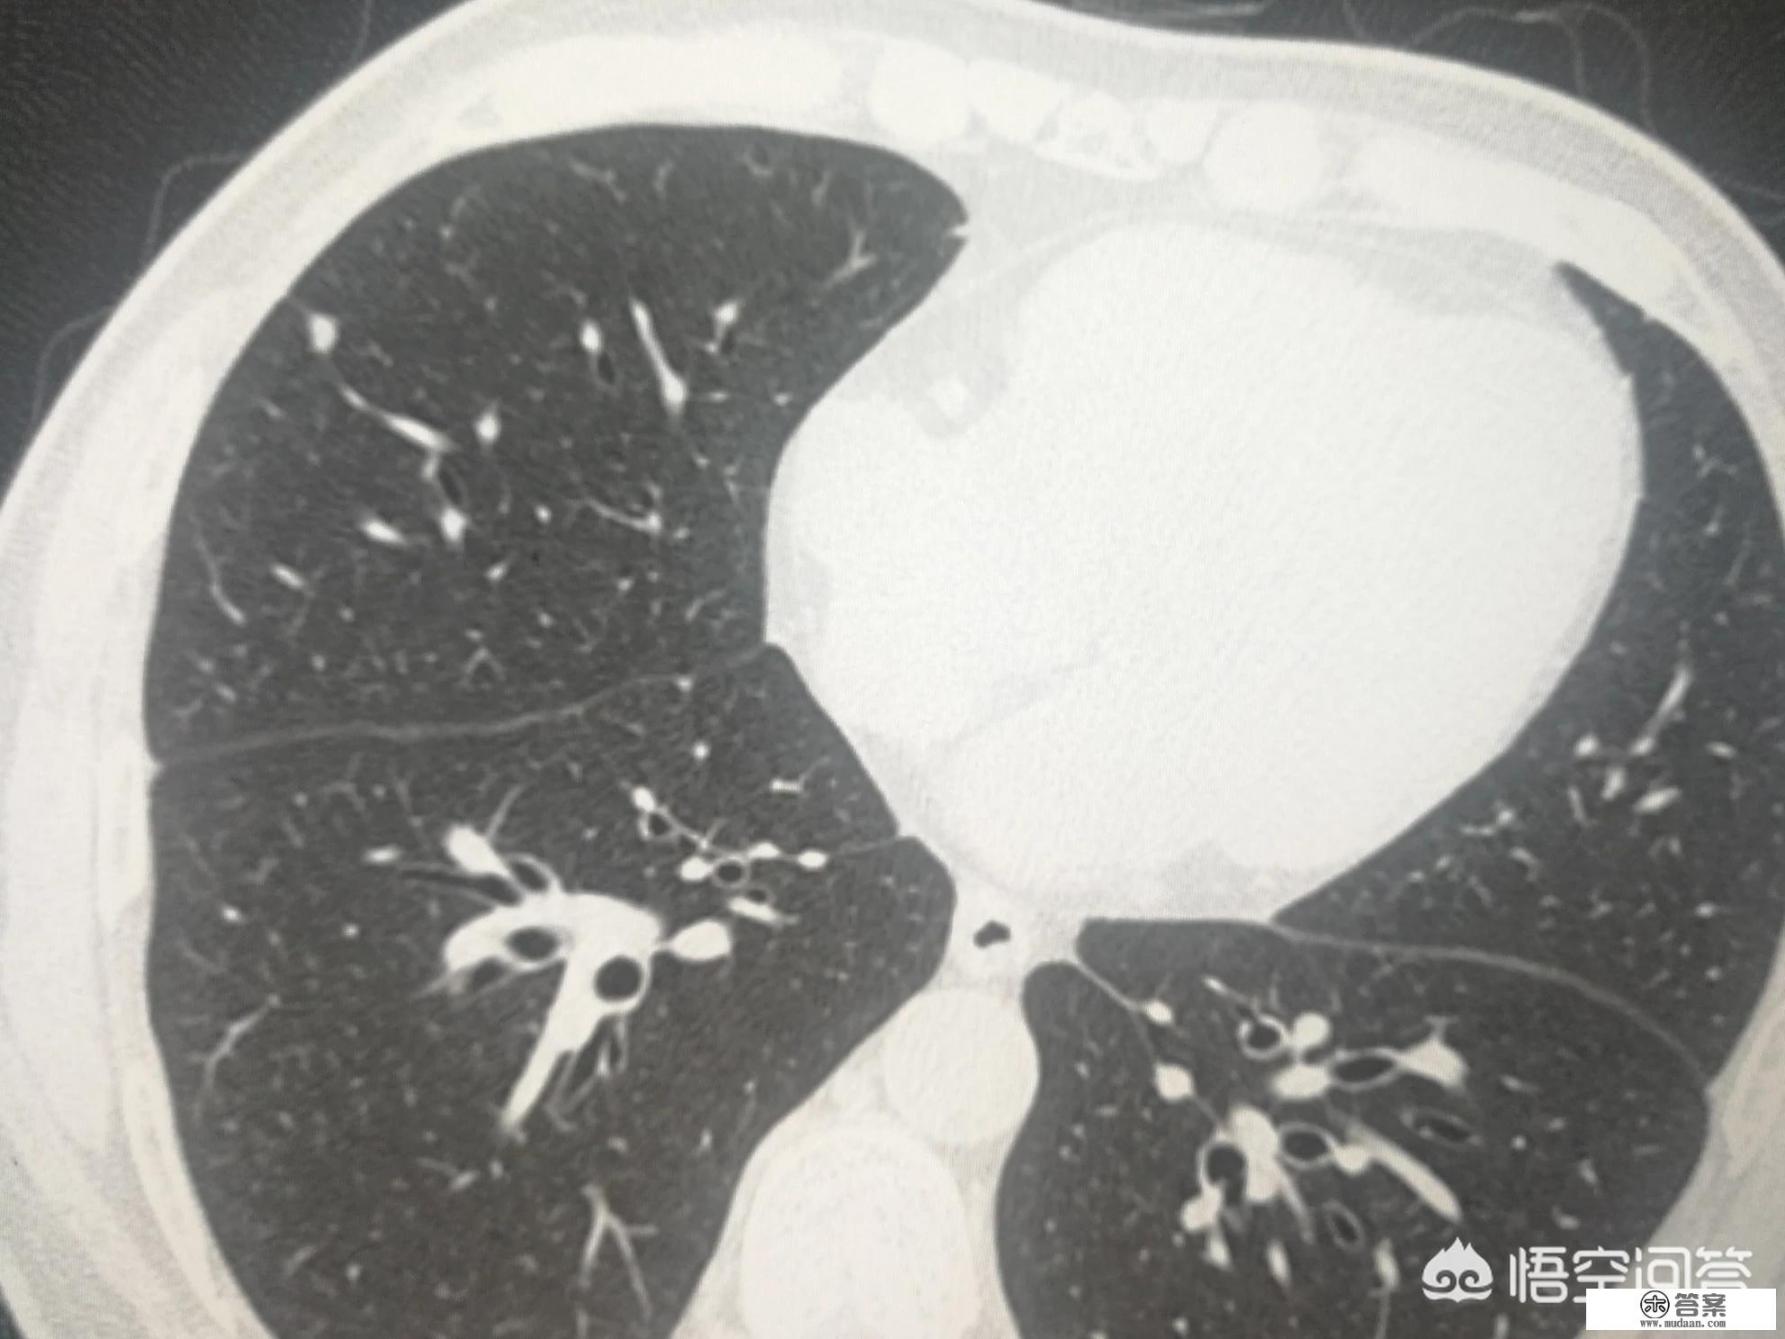

我是杨大夫,肺结节是指影像学上,现代主要是CT发现的。圆形或类圆形的高密度影。

如上图,就是典型的肺内淋巴结。这种典型的结节,CT发现了,也不需要随访复查。但需要放射科大夫的经验和胆识,以及医患双方的互信。